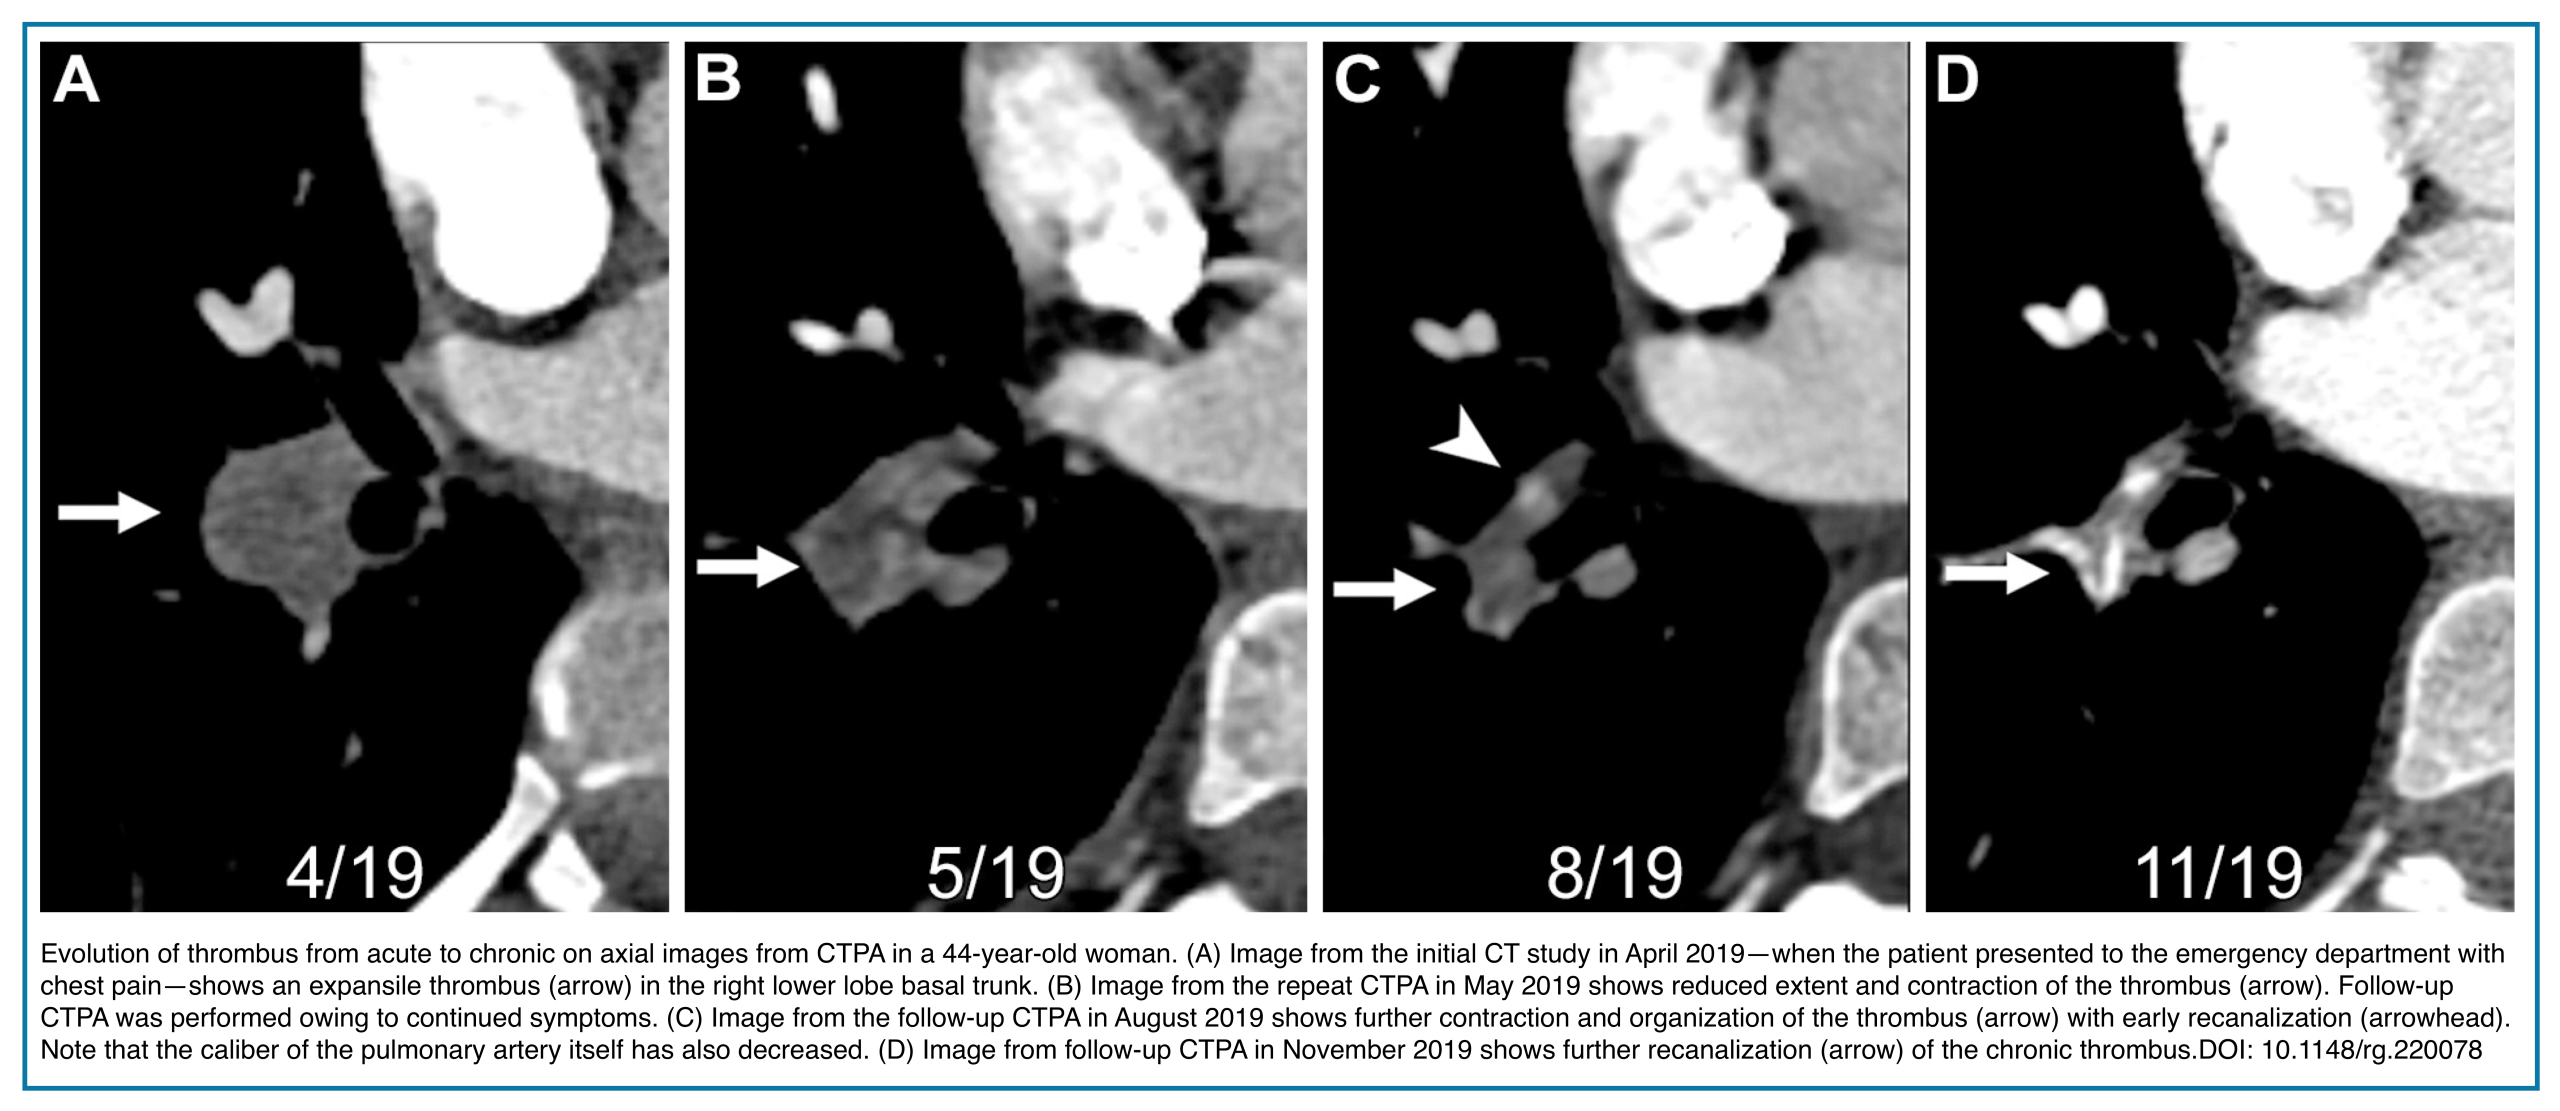

◾️The clot shows signs of organization and recanalization (Below left Figure).

◾️The filling defects in CTEPD can be nonocclusive or occlusive.

- These can appear as linear filling defects that create bands across the pulmonary arteries, which often intertwine to form webs, or as eccentric thrombi forming an obtuse vessel wall margin that may taper into occlusive thrombi more distally (Figure 5).

- They obstruct the vessel lumen and lead to vascular contraction, in contrast to acute thrombus, which distends the vessel.

B. Pulmonary Artery Remodeling

- Vessel shrinkage

- Complete occlusion of a pulmonary artery branch that is permanently smaller than other arteries of the same order (an important distinguishing feature from acute PE, where vessels are often normal or enlarged). Figure 8.